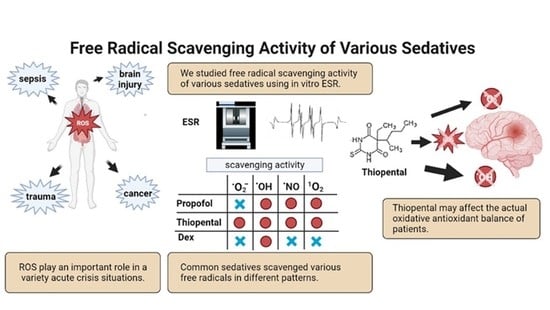

Sedation Therapy in Intensive Care Units: Harnessing the Power of Antioxidants to Combat Oxidative Stress

Abstract

1. Introduction

2.2. In Vitro ESR Method

3. Results

5. Discussion

6. Conclusions and Future Perspectives